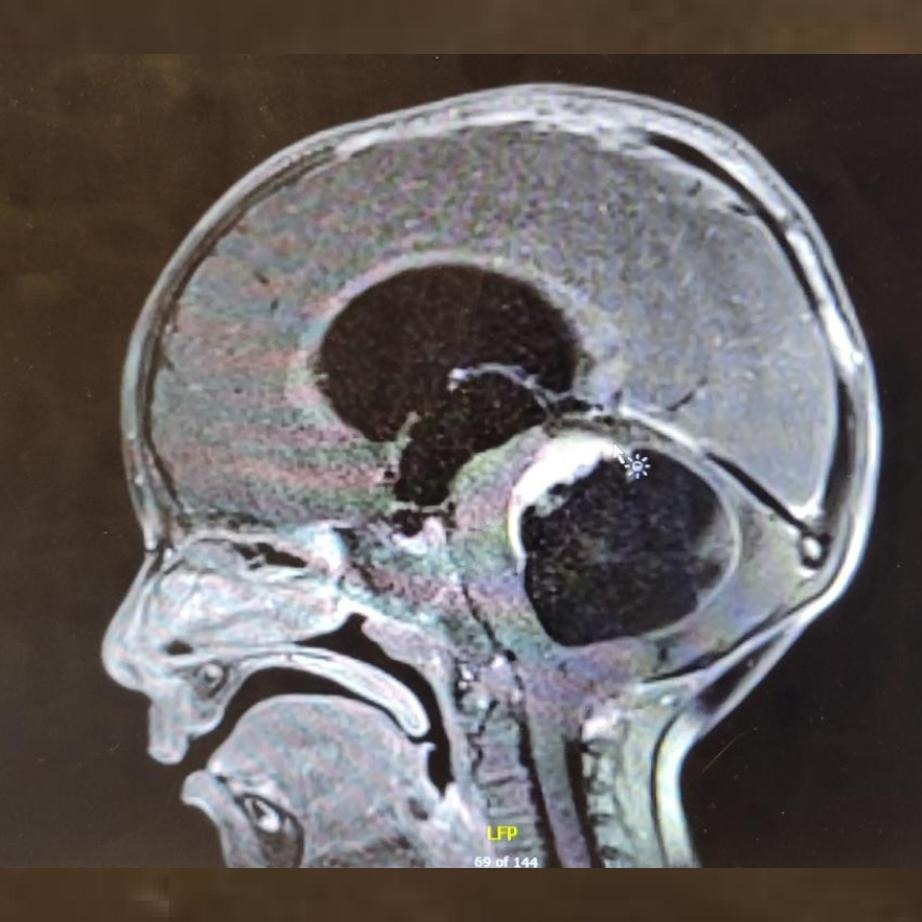

Our son Max was diagnosed with a racquetball-sized pediatric glioma before he turned two. We were terrified.

It was the heroic efforts of St. Jude Children's Hospital and others that gave Max a second shot at life. After an initial emergency surgery in Orlando, a follow-up scan showed the tumor had continued to grow, and we were graciously accepted to St Jude. The entire clinical team at St Jude, led by Dr. Paul Klimo, were singlehandedly responsible for saving Max's life and preserving his autonomy for childhood. Their incredible skill finished a surgery that other hospitals said would be impossible.